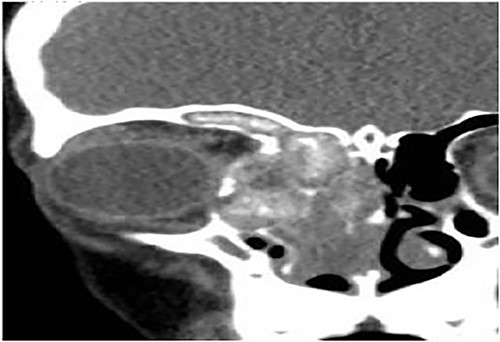

Case 6 (extensive into intraorbital and intracranial structures)

A 15-years-old male presented with bilateral nasal obstruction for a long time associated with nasal discharge, allergic nasal symptoms and headache. Endoscopic nasal examination revealed bilateral extensive nasal polyposis and mucin. CT scan (Fig. 7) and magnetic resonance imaging (MRI) scan (Fig. 8) of the paranasal sinuses confirmed the diagnosis of extensive bilateral allergic fungal pansinusitis with intraorbital and intracranial extradural extension. The patient underwent FESS, and all the polyps, mucin and fungal debris were removed from the sinuses. The patient continued on medical treatment and remained symptoms-free for 5 years follow-up.

Coronal CT paranasal sinuses shows heterogeneous opacities of the ethmoid and maxillary sinuses bilaterally. It is associated with complete opacification and extension through the widened ostiomeatal complex, obliterating the nasal cavities with polyposis. The ethmoid sinuses show expansion with lateral displacement and partial dehiscence of the lamina papyracea bilaterally. The roof of the right ethmoid sinus shows dehiscence with intracranial extension.